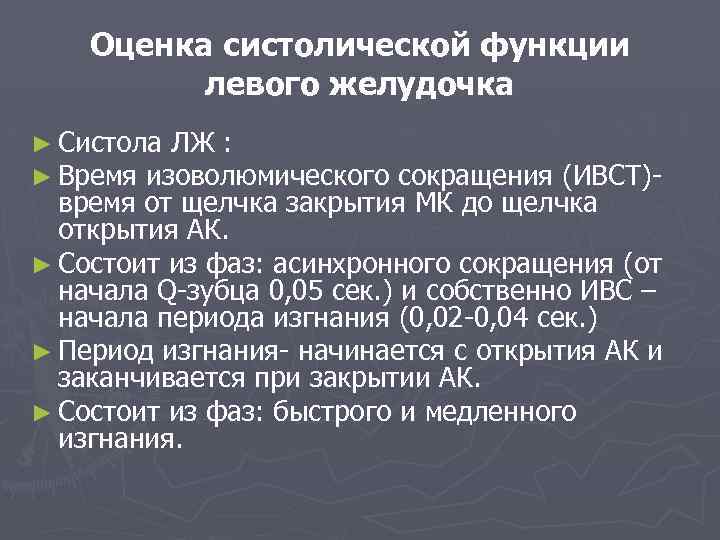

Оценка систолической функции левого желудочка ► Систола ЛЖ : ► Время изоволюмического сокращения (ИВСТ)время от щелчка закрытия МК до щелчка открытия АК. ► Состоит из фаз: асинхронного сокращения (от начала Q-зубца 0, 05 сек. ) и собственно ИВС – начала периода изгнания (0, 02 -0, 04 сек. ) ► Период изгнания- начинается с открытия АК и заканчивается при закрытии АК. ► Состоит из фаз: быстрого и медленного изгнания.